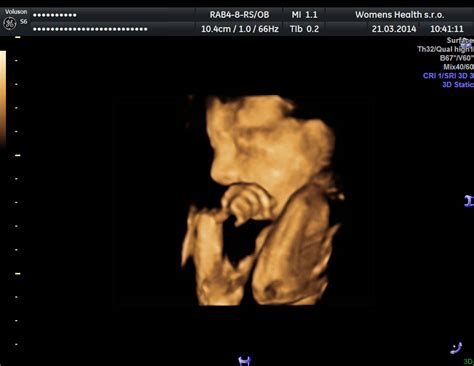

Jediným spoľahlivým spôsobom, ako potvrdiť a určiť počet plodov v maternici, je ultrazvukové vyšetrenie. Už v skorých štádiách tehotenstva (často okolo 8. týždňa) dokáže ultrazvuk odhaliť prítomnosť dvoch (alebo viacerých) zárodkov a ich srdcovej akcie. Neskôr ultrazvuk umožňuje lekárovi skontrolovať počet plodov, ich rast, vývoj a určiť typ dvojčiat (monochoriálne/dichoriálne, monoamniálne/biamniálne) na základe počtu placenty a plodových obalov.